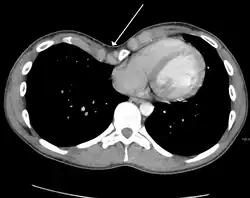

Masses

.jpg)

Masses such as tumors can also cause compression and displacement of mediastinal structures. There are various mediastinal tumors, and they are classified by their location in the chest. Notable examples include germ cell tumors and lymphomas.[12] Teratomas are a class of germ cell tumors that arise in the chest due to failure of germ cell migration during development. They can expand to large sizes and cause hemoptysis and pleural effusion. Radiographic features of teratomas typically include fluid and fat but also muscle, teeth, and bones inside the mass.[13]